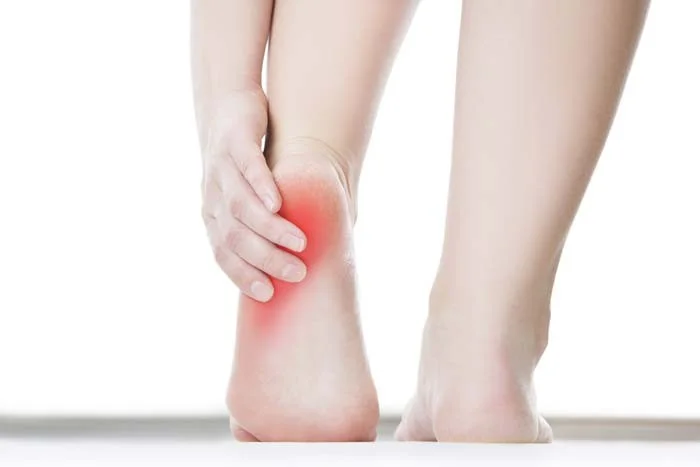

Achilles Tendinitis

Overview

Achilles tendinitis is a condition characterized by inflammation of the Achilles tendon.

Clinical Picture

- Pain: posterior foot / lower leg

- Tenderness:

- Over the lower calf muscle

- Achilles tendon

- Some swelling over the tendon (+/-)